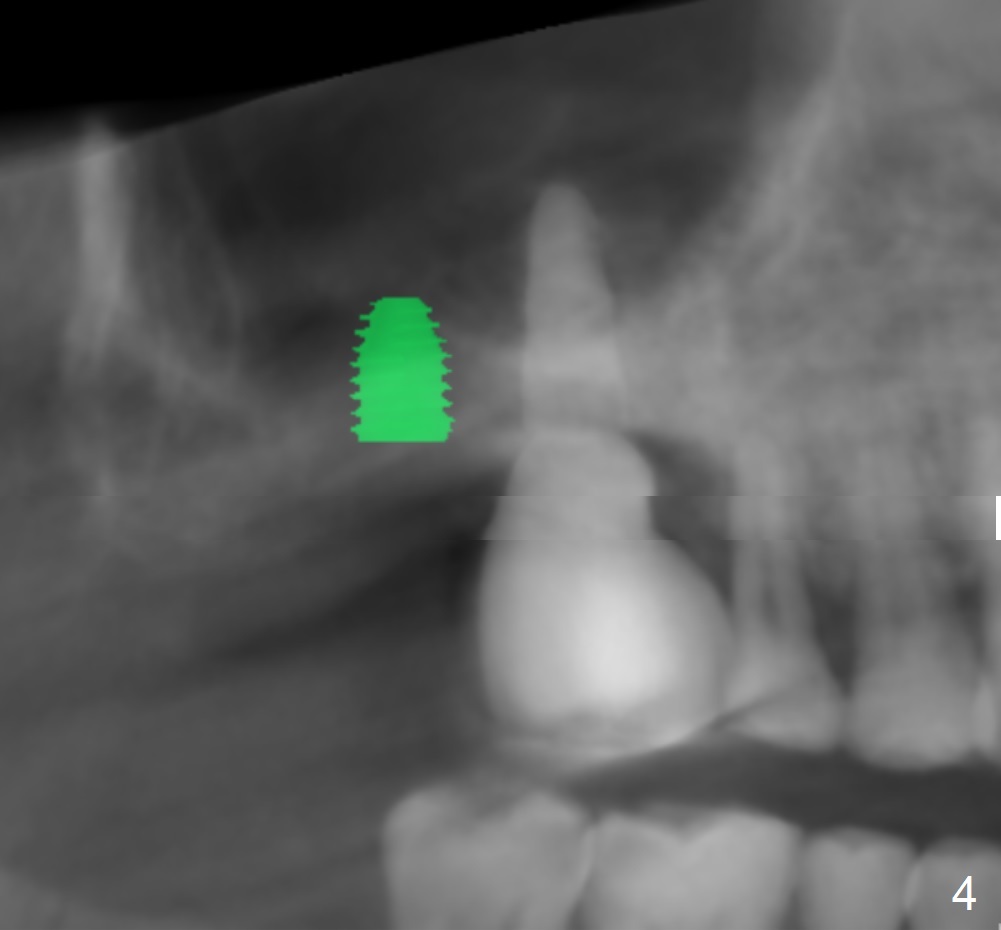

The implant size I tried was 5.0 X 7.3mm and it seems like bone density is quite low.

Undersized drilling suggested (at least 2 size smaller to get more fixation). And on the facial view there's 4mm of remaining bone but on the buccolingual view, there's less than 3mm. It would be much better if you could plan to do a lateral sinus elevation in this case.  Jennifer